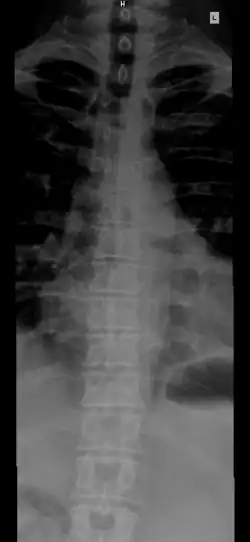

Позвоночник человека

«#» — шейный отдел (Pars cervicalis)

«#» — грудной отдел (Pars thoracalis)

«#» — поясничный отдел (Pars lumbalis)

«#» — крестец (Os sacrum)

«#» — копчик (Os coccygis)

Позвоно́чный столб, или позвоно́чник (лат. columna vertebralis) — основная часть осевого скелета человека. Состоит из 32—33 позвонков, последовательно соединённых друг с другом в вертикальном положении[1][2]. Позвонки разделяют на отдельные типы: шейные, грудные, поясничные, крестцовые (срастаются в крестец) и копчиковые.

Различают 5 отделов позвоночника:

- Шейный отдел (7 позвонков, C1—C7);

- Грудной отдел (12 позвонков, Th1—Th12);

- Поясничный отдел (5 позвонков, L1—L5);

- Крестцовый отдел (5 позвонков);

- Копчиковый отдел (3-4 позвонков)[2], иногда до 5).